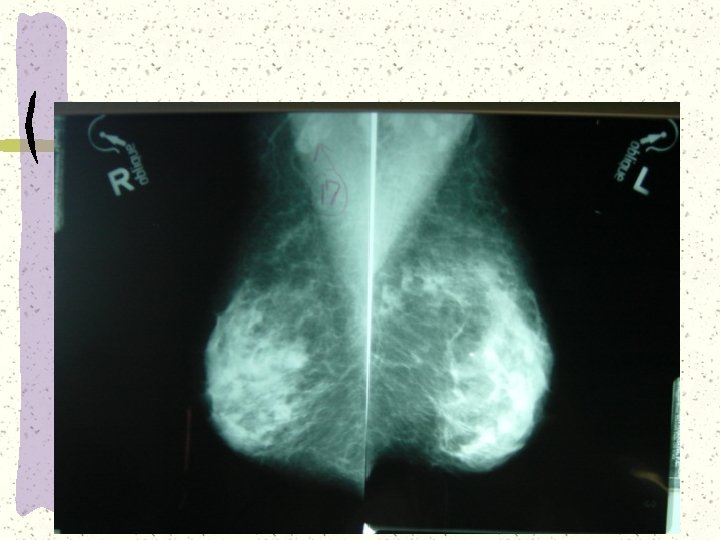

Viewing A Mammogram Right and Left opposite each other for CC and MLO Place

Viewing A Mammogram Right and Left opposite each other for CC and MLO Place comparison films either to the sides or above or below current films Hang anatomically Axillary region always up Marker always in Axillary region